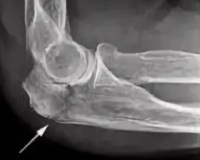

• Рентгенография. Это базовое исследование, выполненное в двух проекциях. На рентгенограммах определяют уровень и вид перелома, наличие смещения отломков. При эпифизеолизе методика часто не очень информативна.